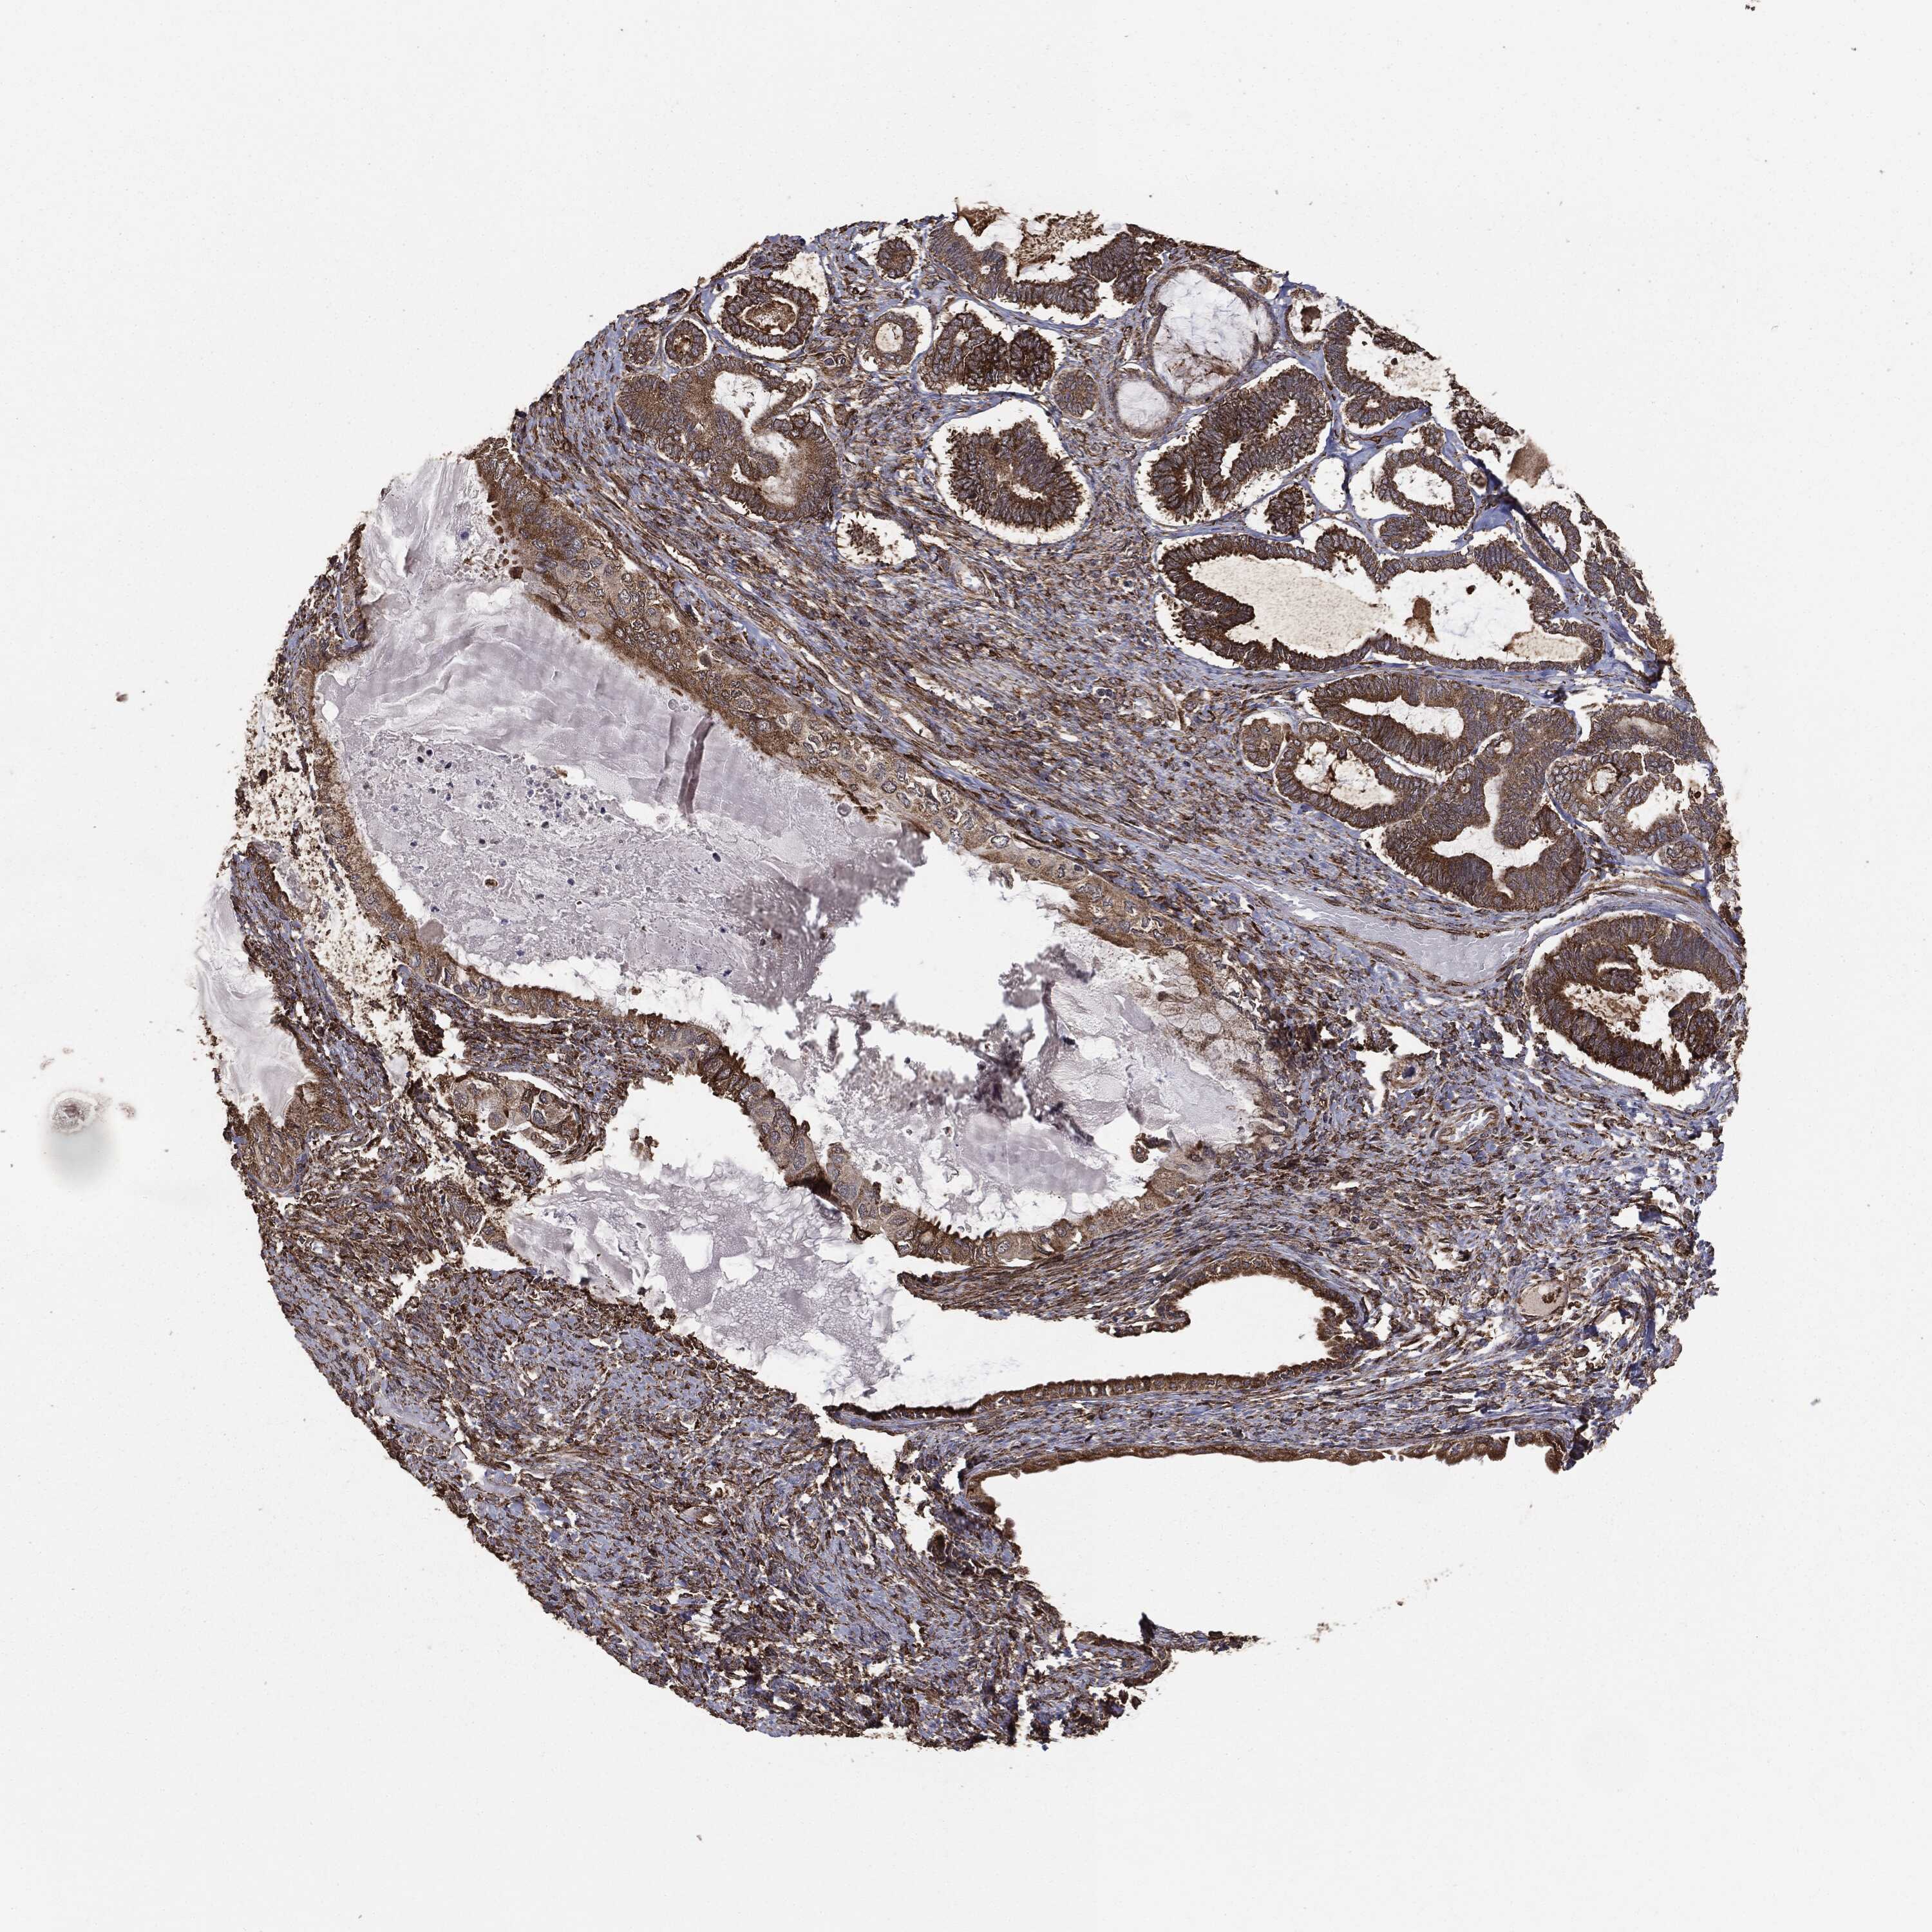

OVARIAN CANCER - Protein expressioni

A mouse-over function shows sample information and annotation data. Click on an image to view it in a full screen mode. Samples can be filtered based on level of antibody staining by selecting one or several of the following categories: high, medium, low and not detected. The assay and annotation is described here.

Note that samples used for immunohistochemistry by the Human Protein Atlas do not correspond to samples in the TCGA dataset.

Antibody stainingi

Antibody staining in the annotated cell types in the current human tissue is reported as not detected, low, medium, or high, based on conventional immunohistochemistry profiling in selected tissues. This score is based on the combination of the staining intensity and fraction of stained cells.

Each image is clickable and will lead to virtual microscopy that enables deeper exploration of all samples and also displays staining intensity scores, fraction scores and subcellular localization as well as patient and tissue information for each sample.

CAB069425